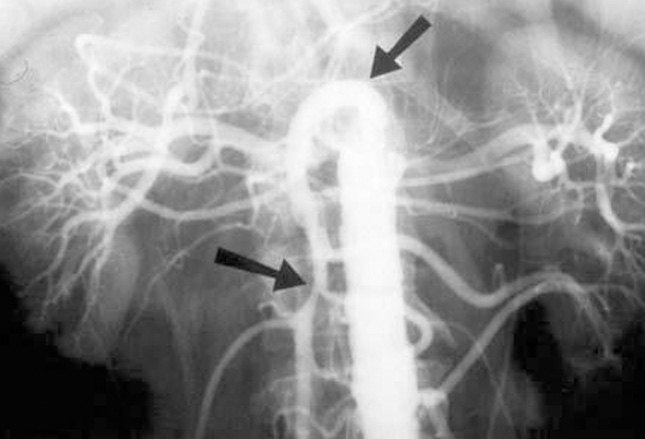

这名患者有急性肠系膜缺血,由肠道供血不足所致。栓塞事件约占所有临床病例的50%。心房颤动

引起的心房血栓、心内膜炎以及斑块通常相关联。由于其较高的流动率和较低的角度,肠系膜上动脉常受影响。栓塞引起的急性肠系膜缺血往往表现为继发于急性阻塞性事件的突然发作的疼痛。

常出现恶心和呕吐。实验室检查是非特异性的,对比增强CT或血管造影

通常是必要的。阻塞性缺血通常经手术治疗,腹膜炎患者需要立即进行手术评估。图像显示的急性静脉肠系膜缺血(左)的CT扫描,显示肠壁增厚,腹腔积液,手术证实肠系膜充血(右)。肠系膜缺血与高死亡率有关(75%)。